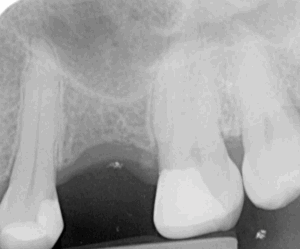

This lady attended Gentle after a previous implant had not worked. In the left photo below is a temporary bridge that kept falling out, which was frustrating for the patient, so she wanted to try again with implant treatment. Moreover, when she smiled, the adjacent eye tooth had an exposed root, so it looked too long. At the same time as placing gum around the implant, a gum graft was placed to cover the exposed eye tooth root. This improves the overall aesthetic outcome for the patient. Below on the right you can see how we took time to rebuild the bone and gum in the first phase of treatment, which gave the implant a solid foundation to sit in.

The implant was placed into the bone, under the gum, and a white post was chosen to fit into the implant to maximise the final crown’s appearance. The after photo was taken 5 years after the implant was placed and shows how nicely the work is performing.